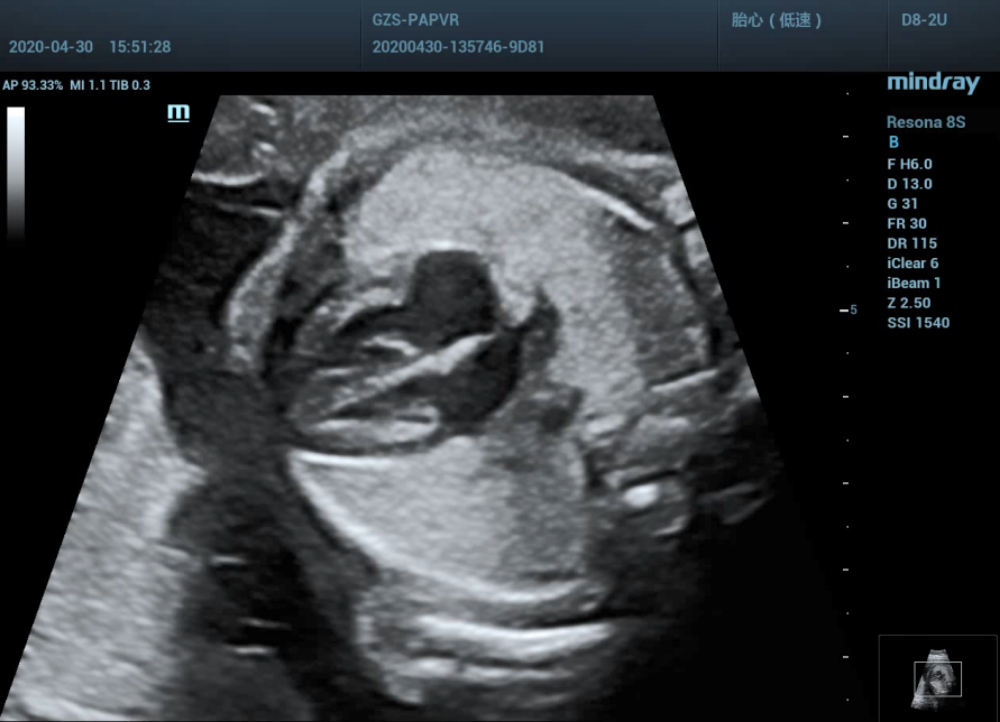

Four-chamber view

•  Concordant atrioventricular connection. Normal ratio of left and right atrium diameter, a little hyperechoic in the LV. Normal shape and function of atrioventricular valve.

By now, everything is normal. The preliminary diagnosis suggested no significant abnormality in fetal heart structure at present. However, when the probe is slightly tilted from the standard four chamber view to the fetal foot side, the problem occurs:

Low-level four-chamber view